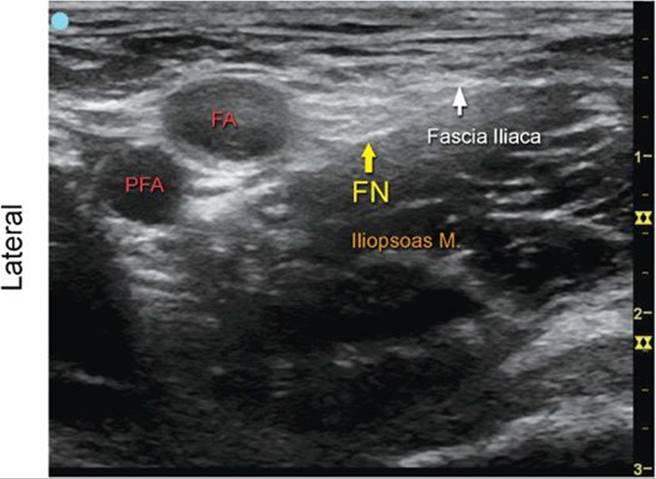

Femoral Nerve, Transverse View

FIGURE 7.49.1A Ultrasound transducer position to image the femoral nerve, transverse view.

FIGURE 7.49.1B Ultrasound image of the femoral nerve, transverse view.

FIGURE 7.49.1C Labeled ultrasound image of the femoral nerve, transverse view.

FIGURE 7.49.1D Labeled cross-sectional anatomy of the femoral nerve at the level between inguinal ligament and femoral crease.

Abbreviations: FA, Femoral Artery; PFA, Profunda Femoris Artery; FN, Femoral Nerve; FV, Femoral Vein.